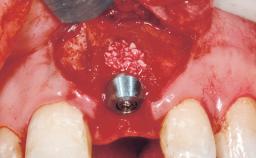

# of Implants 1

Type of Implants Two-Piece

Bone Augmentation Horizontal|Staged

Augmentation Materials Xenogenous|Membrane

Placement Protocol Early or late implant placement